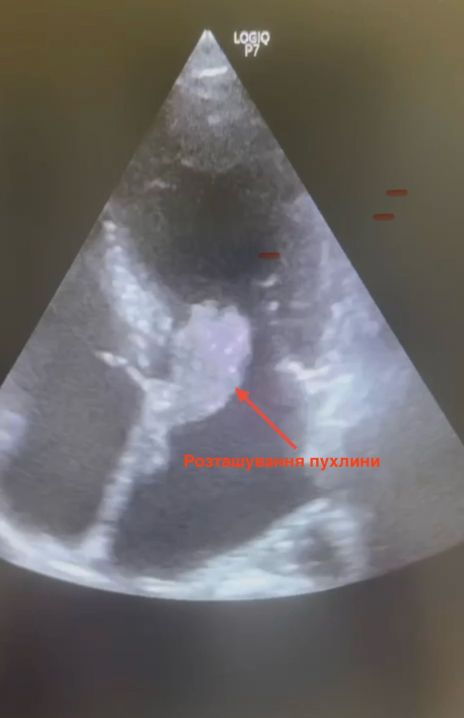

Життя буковинки врятували кардіохірурги Чернівецької обласної клінічної лікарні. Під час складної операції лікарі видалили з її серця рідкісну пухлину – міксому лівого передсердя, розміром 2,5×5 см.

"У цьому випадку пухлина була особливо загрозливою, оскільки мала желеподібну структуру і не була капсульованою. У будь-яку мить могла фрагментуватися та спричинити інфаркт або інсульт. Такий стан становить серйозну небезпеку для життя, – розповідає лікар-кардіохірург ОКНП «Чернівецька обласна клінічна лікарня» Андрій Перепелюк. – Завдяки злагодженій роботі команди лікарів вдалося своєчасно усунути загрозу й врятувати життя молодій жінці".

Пухлину серця у буковинки виявили випадково – під час профілактичного УЗД-обстеження. Це ще раз доводить: своєчасна консультація лікаря може врятувати життя.